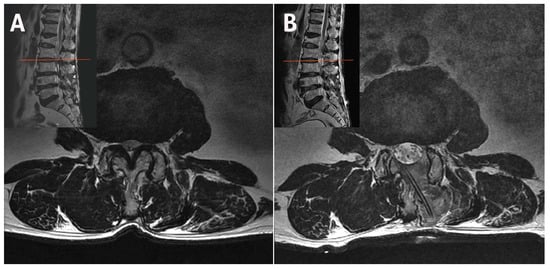

2.3. Case 3: Bilateral–Contralateral Decompression in Spondylolisthesis

| 3 | 78 | F | Stenosis with Spondylolisthesis | L3–L4 | 64 | 6 | 2 | 8 | 2 | 50 | 20 | None | 6 |